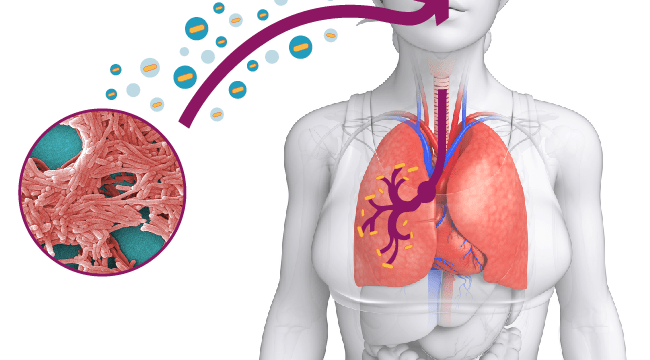

Si tratta di una “famiglia” di batteri, ne esistono più di 50 specie. La più pericolosa è la Legionella pneumophila. Questi microrganismi proliferano nell’acqua: fiumi, laghi, impianti idrici cittadini. Possono però essere presenti anche nel terreno. Diventano un problema in condizione di stagnazione e in particolare d’estate, quando la temperatura dell’acqua supera i 25 gradi. La Legionella pneumophila provoca la legionellosi, anche conosciuta come malattia del legionario, un’infezione polmonare. Non si trasmette da persona a persona, ma attraverso l’inalazione di acqua contaminata sospesa in aerosol nell’aria. La contaminazione da legionella può manifestarsi in forma meno grave e in questo caso prende il nome di febbre di Pontiac. Febbre che si manifesta generalmente entro uno o due giorni dal contagio. La legionellosi vera e propria ha invece un periodo di incubazione più lungo, di 5 o 6 giorni. Come spiega l’Istituto Superiore di Sanità, l’infezione “pone un serio problema di salute pubblica, perché costituisce un elemento di rischio in tutte le situazioni in cui le persone sono riunite in uno stesso ambiente, come case di cura, ospedali, piscine e terme e altri luoghi pubblici, in cui è in funzione un sistema di condizionamento, umidificazione, trattamento dell’aria o ricircolarizzazione delle acque”.

La legionellosi può presentarsi con alcuni dei sintomi tipici dell’influenza. Nei casi meno gravi è spesso confusa proprio con questa malattia. Infatti si manifesta attraverso: febbre, brividi di freddo, tosse secca o grassa, dolori muscolari, mal di testa, stanchezza, inappetenza e diarrea (più raramente). Quando si manifesta come Febbre di Pontiac, i sintomi sono febbre e dolori muscolari, che scompaiono nel giro di qualche giorno. Come abbiamo visto, purtroppo, nei casi più gravi si presenta come una forma molto forte di polmonite e, nei soggetti con un sistema immunitario già debole, può portare alla morte. Una volta manifestatasi la malattia, il trattamento comune è quello della terapia antibiotica.